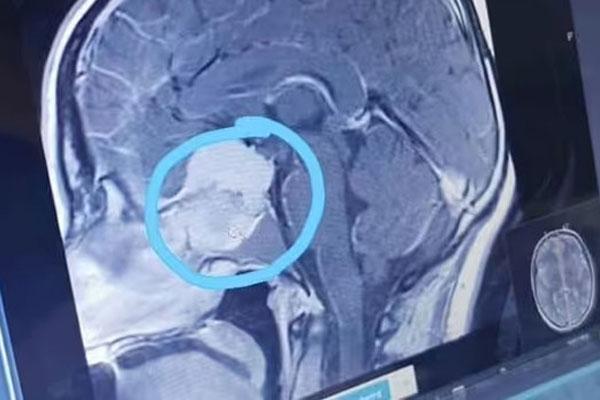

Katie không hề biết sự tồn tại của khối u cho tới khi đi khám mắt. Ảnh: Express

Theo Express, kết quả chụp chiếu của Katie cho thấy một khối u lớn trong não của cô vào tháng 2/2021. Kể từ đó, cô đã trải qua hai cuộc phẫu thuật và quá trình bảo tồn khả năng sinh sản trước khi bắt đầu xạ trị vào tháng 12/2022.